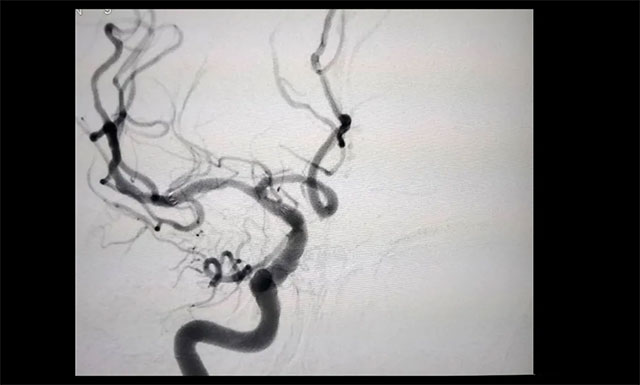

▲ 治療后狹窄明顯改善

經(jīng)過與醫(yī)院腦血管病病區(qū)主任張琪博士團隊開展評估會診,在醫(yī)院DSA系統(tǒng)的支持下,由張琪博士為胡老伯行右側大腦中動脈球囊擴張及支架置入手術。術中造影觀察可見,狹窄明顯改善,血流也隨即恢復了通暢。